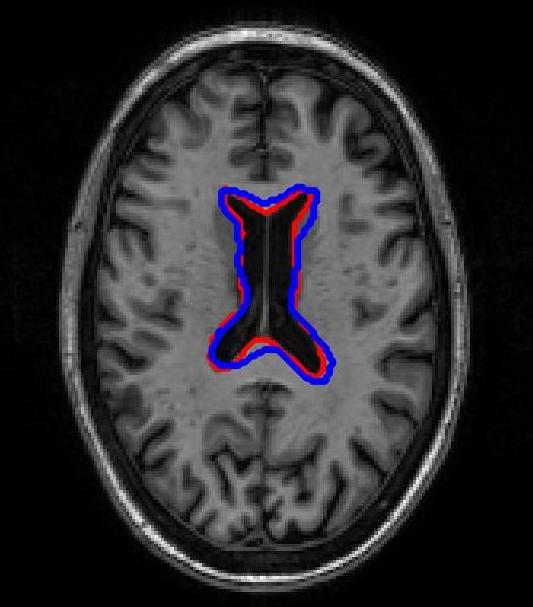

FigureΒ 3 shows results for brain image registration. We show the reference image in FigureΒ 3 (a) followed by an example floating image in FigureΒ 3 (b). The ventricle structure to be aligned is shown in red in both images. FigureΒ 3 (c)-(e) shows the deformed structures obtained by applying the registration field obtained from different methods to the floating image and superimposing these structures on the atlas image. The deformed structures from the floating image are shown in blue. In case of perfect registration the blue and red contours should coincide. In this case SR-Net actually does better than VoxelMorph, while SR-Net does significantly worse due to absence of segmentation information.

![]() |

| (a) | (b) | (c) | (d) | (e) |